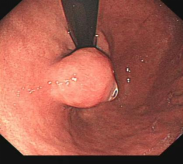

胃内4x4cm粘膜下隆起,胃镜下完整切除(ESE),术后病理证实平滑肌瘤,保留胃正常组织结构。

内镜手术展示